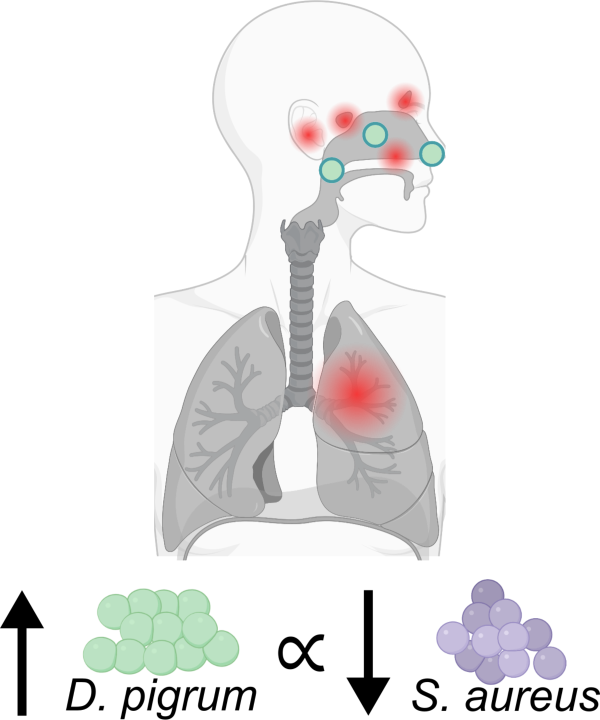

The long-term goal of this work is to understand the chemical mechanisms used by Dolosigranulum pigrum, a beneficial bacterial species found in the human nose, to compete against co-occurring Staphylococcus aureus, and to develop therapeutics against this pathobiont. The overall objectives in this application are to (i) isolate and identify ribosomally synthesized and post-translationally modified peptides (RiPPs) that are produced by D. pigrum to inhibit S. aureus and (ii) establish a genetic system for D. pigrum that will enable future research into this beneficial organism.